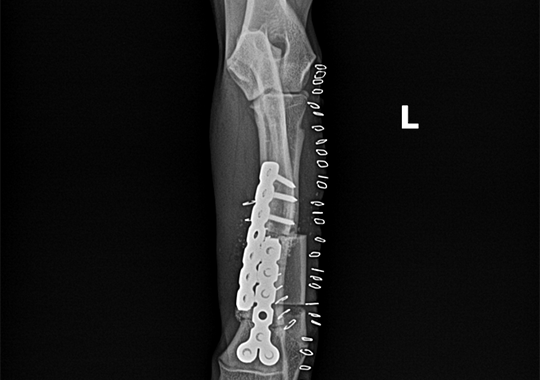

정형외과 케이스

본원은 실력 있는 전문 의료진과 최첨단 시설로 정형외과에서 좋은 예후들을 보여드리고 있습니다. 강아지에게서 쉽게 발생하는 슬개골 탈구, 십자인대 단열 뿐 아니라 다양한 고난도 케이스를 다루고 있으며, 특히 골절 수술은 회복률이 높고 타원 수술 후, 유합부전으로 본원에 내원하여 재수술에 성공한 사례가 많습니다.

요척골 복합만곡기형 수술 전

요척골 복합만곡기형 수술 후

타원 실패 수술 후 2차 수술 전

타원 실패 수술 후 2차 수술 후